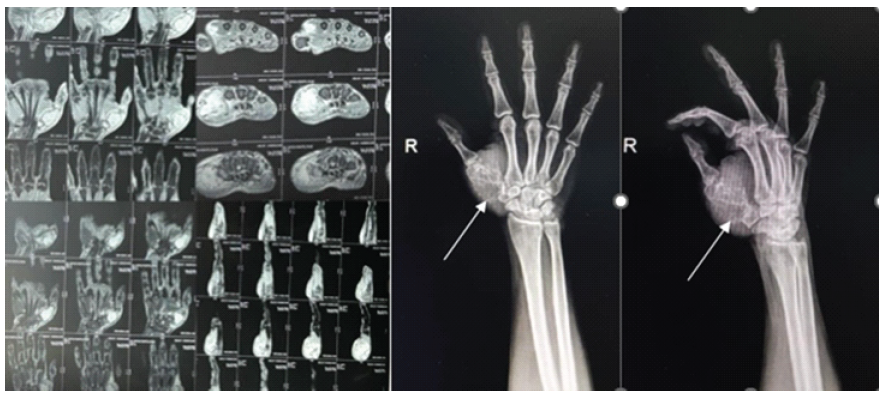

Magnetic resonance imaging was suggestive of a lytic expansile enhancing lesion involving the right 1st metacarpal bone with thinning and break in overlying cortex with associated soft-tissue swelling measuring approximately 3.9 × 3.0 × 4.4 cm in size with the lesion not crossing the 1st carpo-metacarpal joint (Fig. 2). The plan was to excise the lesion in toto and replace the defect with a tri-cortical bone graft from the iliac crest, and send the sample for histopathological study with the differential diagnosis including – CMF, giant cell tumor, and enchondroma.

Figure 2: Pre-operative magnetic resonance imaging and X-rays.